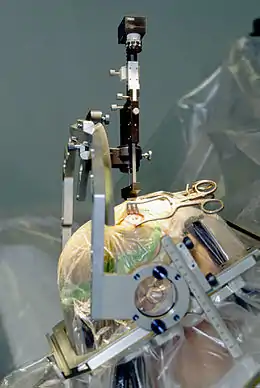

A doctor performing Stereotactic Gamma Knife Radiosurgery, a non-invasive procedure

A doctor performing Stereotactic Gamma Knife Radiosurgery, a non-invasive procedure Puma Robotic Arm

The main advancements in neurosurgery came about as a result of highly crafted tools. Modern neurosurgical tools, or instruments, include chisels, curettes, dissectors, distractors, elevators, forceps, hooks, impactors, probes, suction tubes, power tools, and robots.[24][25] Most of these modern tools have been in medical practice for a relatively long time. The main difference of these tools in neurosurgery, were the precision in which they were crafted. These tools are crafted with edges that are within a millimeter of desired accuracy.[26] Other tools, such as hand held power saws and robots have only recently been commonly used inside of a neurological operating room. As an example, the University of Utah developed a device for computer-aided design / computer-aided manufacturing (CAD-CAM) which uses an image-guided system to define a cutting tool path for a robotic cranial drill.[27]